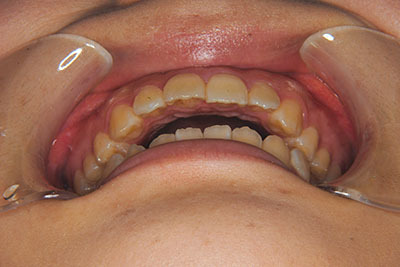

おとなの方でも矯正治療をあきらめないでください!

子供の頃に矯正治療を行う方が治療期間が短く済むというのは、確かですが、矯正治療は患者様の意識も重要です。

いくら歯が動き易くとも、本人がやる気でなければ効果は出ませんし、むし歯発生のリスクも高まります。おとなの方は顎の成長が終わっているため、治療の計画が立てやすいとも言えます。「もう大人だから…」とあきらめず、一度ご相談ください。